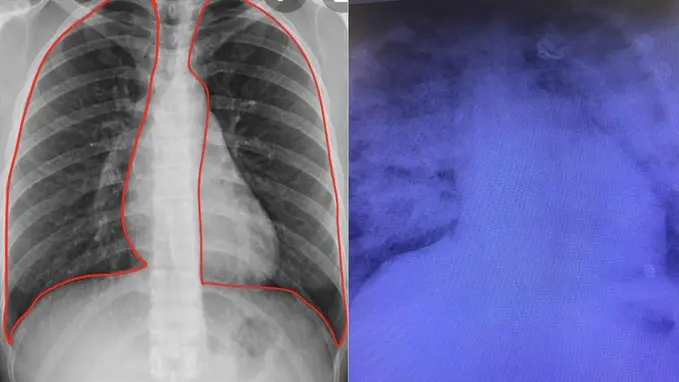

Todas las habitaciones de la sala respiratoria están ocupadas por seis pacientes, incluida una señora de 74 años, quien contó: “El viernes pasado no podía abrir los ojos", reveló. “Caminar entre el salón y mi habitación era imposible. Mi hijo me llevó primero a urgencias del Hospital Popular, pero había tanta gente que no podíamos ni sentarnos. Luego me hicieron una radiografía de los pulmones. Me dijeron: ‘Tus pulmones se han vuelto blancos, todas las partes están infectadas’. Mi hermana pequeña se asustó cuando vio esto. No sé cómo lo hizo, ¡pero me encontró un sitio aquí!”, agregó.

Pulmones blancos

El coronavirus está provocando manchas blancas en los pulmones. "Mi padre tiene 74 años. Esta vez está demasiado enfermo. Sus pulmones están blancos. He visto a otros pacientes en la sala que también tienen los pulmones blancos. Pero con síntomas más leves, es posible superarlo. En este caso, no lo sabemos. Se lo llevaron, pero los médicos dicen que no hay nada seguro. No se lo hemos dicho a mamá", se sinceró la hija de un paciente internado en grave estado.

Las manchas blancas en los pulmones provocadas por el coronavirus

¿Qué son los "pulmones blancos"?

El doctor Joaquín Lamela López explicó en el sitio web TopDoctors.es que "las ’manchas en los pulmones’ son opacidades o densidades ’blanquecinas’ que se ven en la radiografía o TAC de tórax y pueden deberse a distintas enfermedades. Las infecciones pulmonares son la causa más frecuente de opacidades en los pulmones".

"Otras enfermedades más raras también las causan, como sarcoidosis y neumonía organizada criptogénica, y otras más frecuentes como el edema pulmonar, embolia pulmonar y cáncer de pulmón. Estas opacidades aparecen cuando no entra aire por el bronquio o cuando una infección, tumor u otra enfermedad ocupan los alvéolos o saquitos aéreos pulmonares", detalló el experto en neumonología. /Perfil